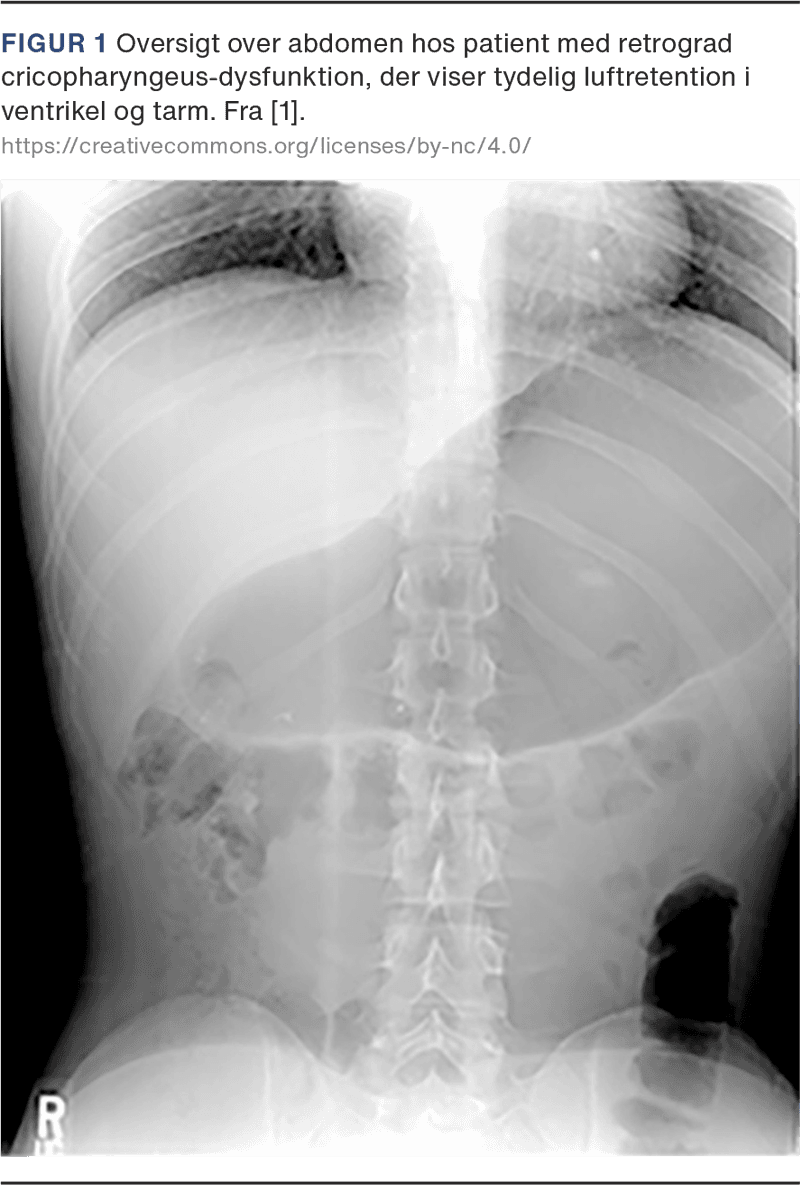

Retrograd cricopharyngeus-dysfunktion (R-CPD) som nyt syndrom blev første gang beskrevet af Bastian & Smithson i 2019. Denne tilstand er associeret med manglende evne til at bøvse og medfører gurglende lyde i halsen, smerte eller en trykkende fornemmelse i brystkassen og maven, oppustet mave, øget flatulens, besvær med at kaste op samt social isolation på grund af de nævnte symptomer (Figur 1) [1].